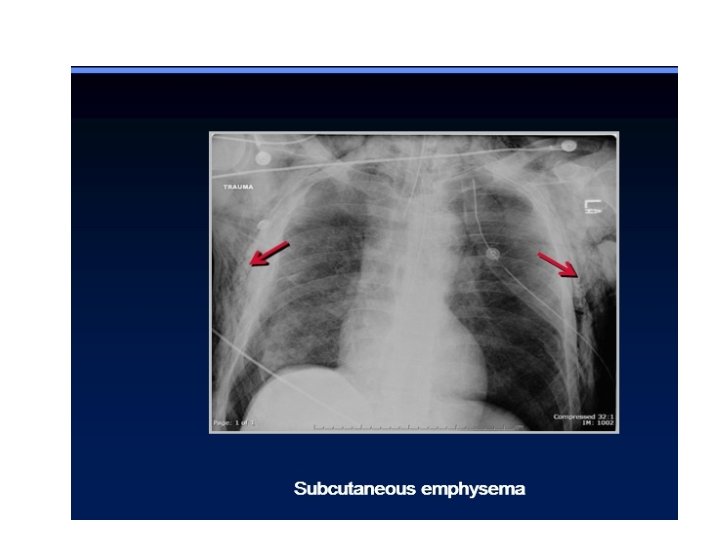

Pulmonary contusion may mask pulmonary laceration on plain chest film. . Associated flail chest

Pulmonary contusion may mask pulmonary laceration on plain chest film. . Associated flail chest and sub cut. Emphysema